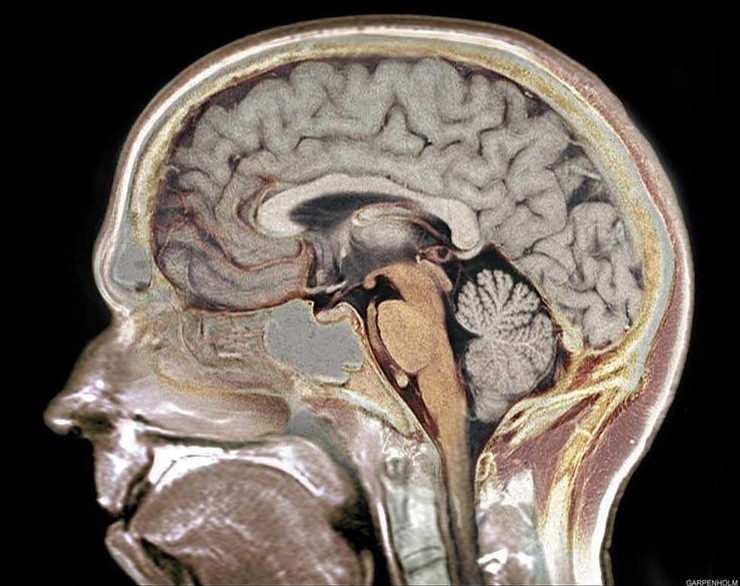

3. Некоторые люди прожили почти обычную жизнь, практически не имея мозга

Мозг принято считать главным органом человеческого тела, без которого невозможно нормальное существование. Однако в медицинской практике зафиксированы случаи, которые ставят это убеждение под сомнение.

Один из самых поразительных примеров — история 44-летнего француза, обратившегося к врачам с жалобами на слабость в ноге. Обследование показало, что большая часть его мозга была замещена жидкостью из-за хронического нарушения оттока спинномозговой жидкости. Фактически у него оставалось около 10% мозговой ткани.

При этом мужчина был женат, воспитывал двоих детей и имел IQ около 75, что не считается тяжёлым интеллектуальным нарушением. Подобные случаи фиксировались и в других странах: например, у женщины из Китая полностью отсутствовал мозжечок, а у другого пациента функционировал практически один лишь ствол мозга. Эти истории до сих пор вызывают удивление и пересмотр представлений о возможностях человеческого организма.